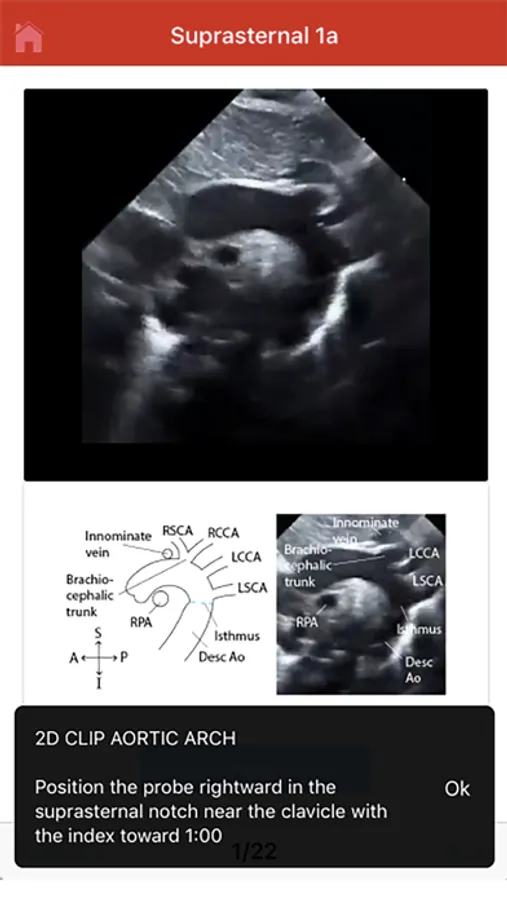

The Echo app provides step-by-step instructions for performing a normal pediatric echocardiogram and uses video clips, images and illustrations to aid in instruction. The app is intended to be used by sonographers at all levels of training, pediatric cardiology fellows, as a teaching aid for pediatric cardiologists and by anyone interested in learning how to perform the normal pediatric echo exam.

The exact images and the order in which the images and views are obtained varies by institution. Each protocol (subcostal, parasternal, apical or suprasternal) can be followed in order by clicking on the next tab at the bottom of the page or you can click on an individual numbered view within the protocol list to be taken directly to that view. The name of the view and instructions will pop-up automatically at the bottom of the page. The instructions and additional notes can also be found in the “NOTE” button at the bottom of the page.